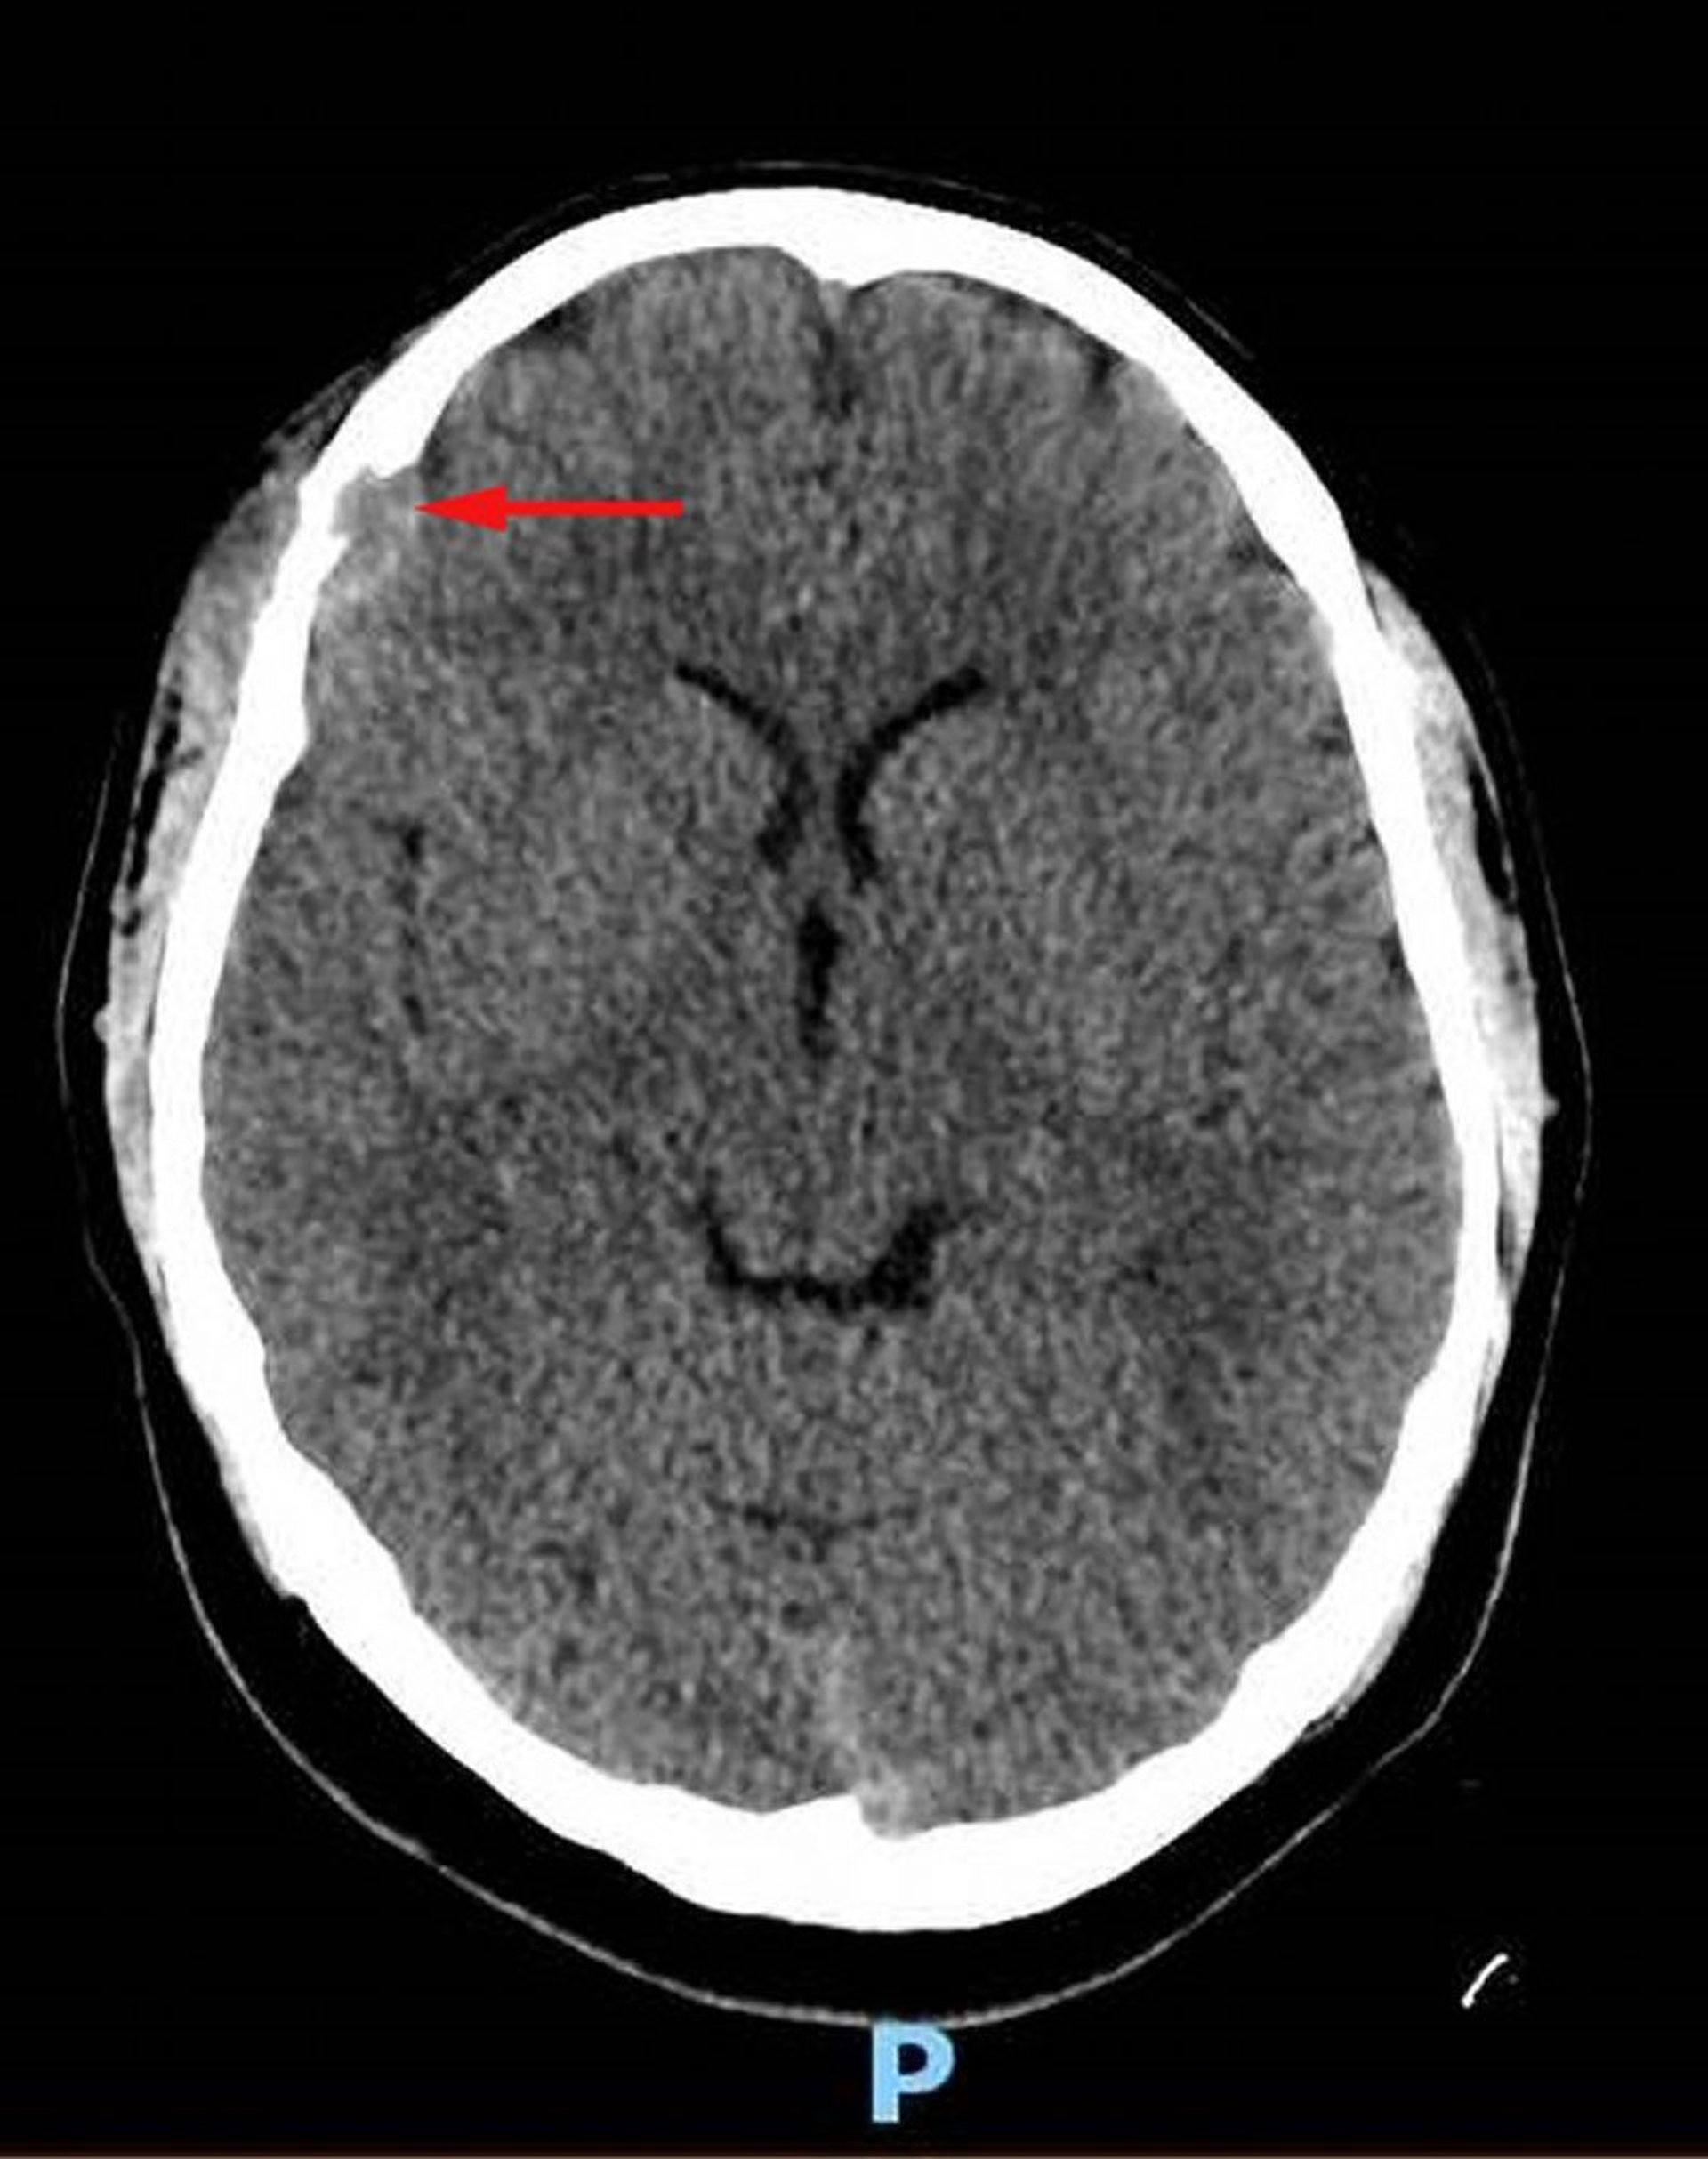

Histiocytose à cellules de Langerhans (TDM de la tête)

Cette image montre une lésion des tissus mous au niveau de l'os frontal droit avec destruction osseuse associée et extension intracrânienne des tissus mous dans l'espace dural (flèche rouge). Un tissu mou du cuir chevelu asymétrique est présent. La biopsie a été diagnostique pour l'histiocytose à cellules de Langerhans.

Image courtoisie de Carolyn Fein Levy, MD, and Jeffrey M. Lipton, MD, PhD.